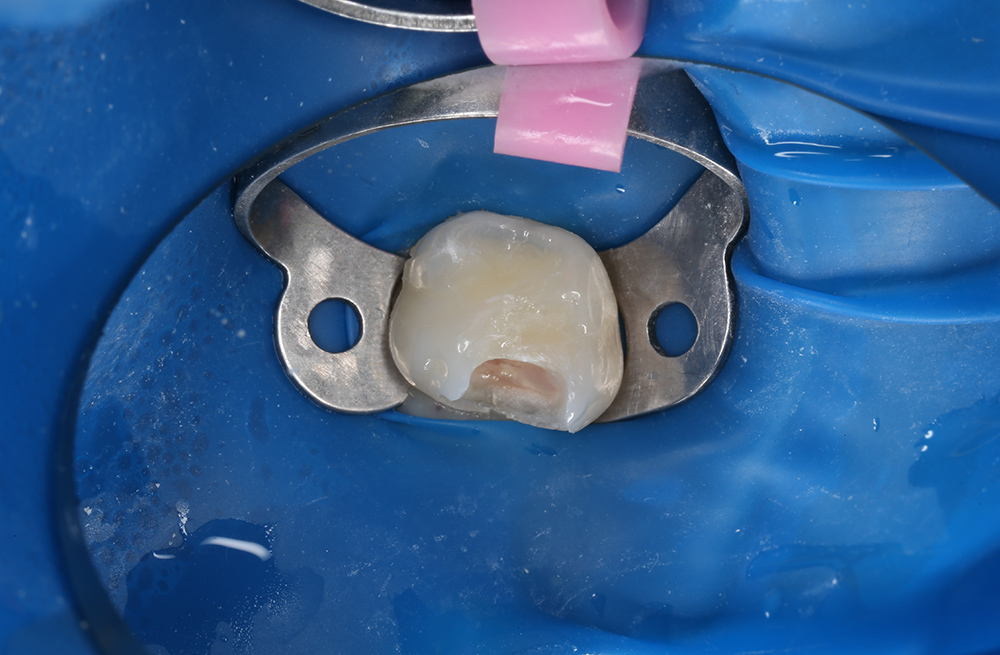

Пломбирование кариозного дефекта коренного зуба с сохранением здоровых тканей